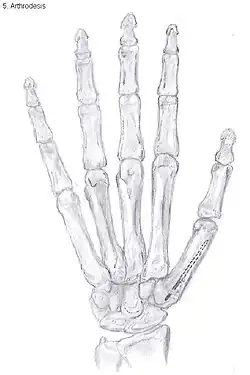

Arthrodesis

Arthrodesis of the TMC joint is a surgical procedure in which the trapezium bone and the metacarpal bone of the thumb are secured together. They are held together by K-wires or a plate and screws until the bone will heal.

Disadvantages include inability to flatten the hand.[27] Additionally, the stress on the CMC joint is now spread over the adjacent joints, those joints are more likely to develop osteoarthritis.[34]

Nevertheless, this procedure can be used in patients with stage II and III CMC OA as well as in young people with posttraumatic osteoarthritis.[27]

After arthrodesis, non-union, in which fusion of the trapezium bone with the metacarpal bone fails, occurs in 8% to 21% of the cases.[27]